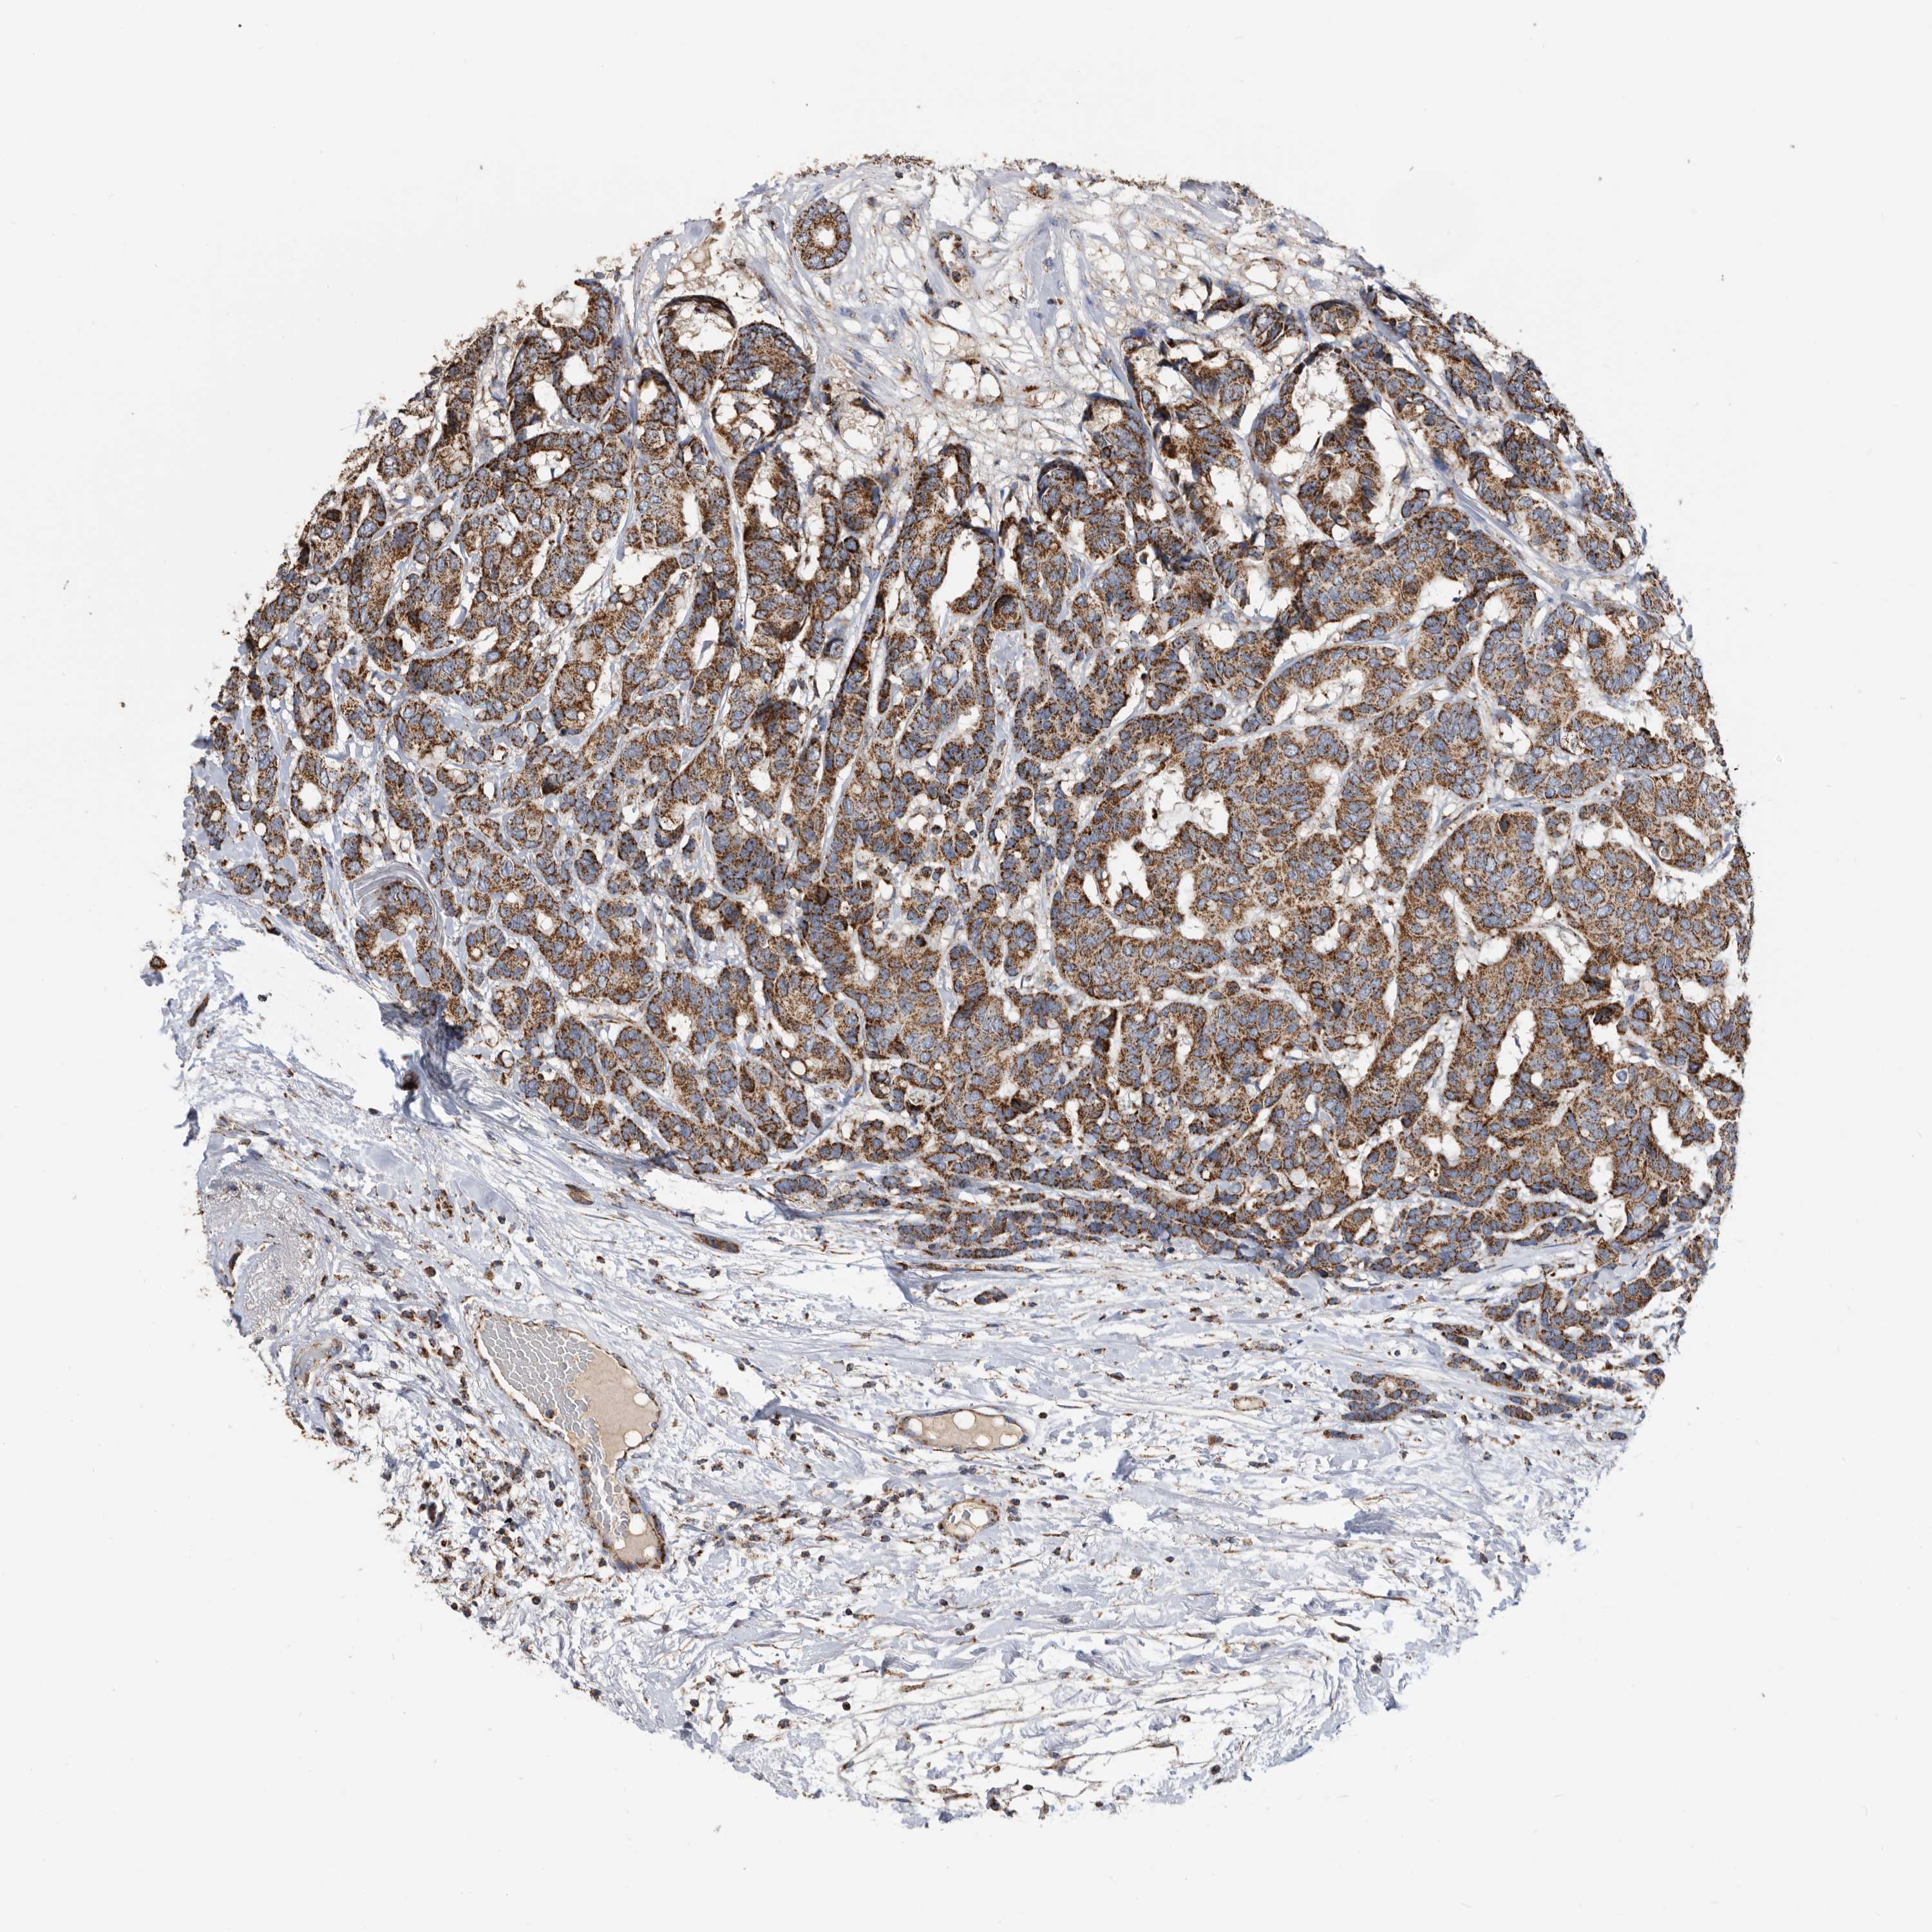

CANCER BREAST CANCER Show tissue menu

BRCA TCGA BRCA VALIDATION PROTEIN EXPRESSION

Breast cancer

Human cancer

Breast invasive carcinoma